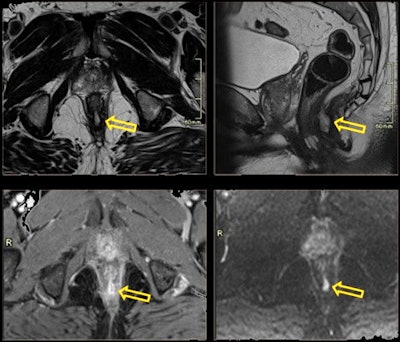

In their analysis, they identified the following genitourinary incidental findings:

- Lymphangioma: presacral cystic lesions

- Bone lesions, fractures, bursitis, degenerative osteoarthritis of the hip, and metastatic or primary bone lesions